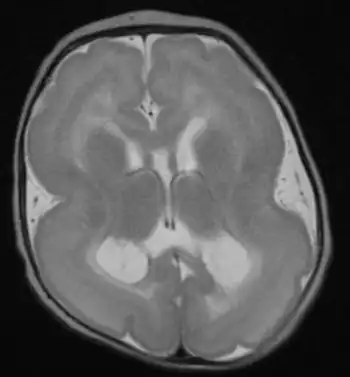

Lissencephaly (/ˌlɪs.ɛnˈsɛf.əl.i/, meaning "smooth brain")[1] is a set of rare brain disorders where the whole or parts of the surface of the brain appear smooth.[2] It is caused by defective neuronal migration during the 12th to 24th weeks of gestation resulting in a lack of development of brain folds (gyri) and grooves (sulci).[3] It is a form of cephalic disorder. Terms such as agyria (no gyri) and pachygyria (broad gyri) are used to describe the appearance of the surface of the brain.

Symptoms of lissencephaly are detected via ultrasound at about twenty-three weeks and require confirmation from a prenatal MRI. It is characterised by absence or reduction of the sulci and gyri of the cerebral surface and a thickened cortex.[5]

There are anatomical symptoms that differ across the two main types of lissencephaly, Classical (Type I) and Cobble Stone (Type 2). In Classical lissencephaly the cortex becomes thickened and can be identified by four layers of the cerebral cortex rather than six.[5]

Cobblestone lissencephaly is named after the pebbled or cobblestone appearance of the cortical surface. This uneven cortical surface is due to incomplete organogenesis which leads to no distinguishable layers in the cerebral cortex. Cobblestone lissencephaly shows a reduction and abnormalities in the grey matter of the cerebral cortex.[5]